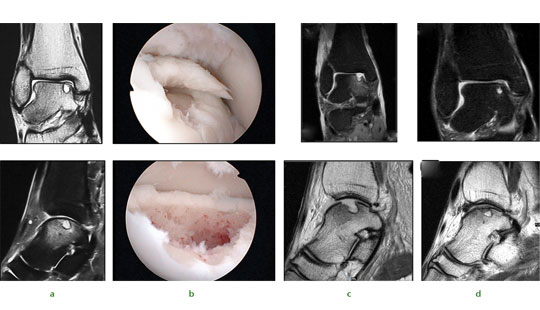

Stem cell therapy is not just applicable to the knee, however, and we have successfully applied this technique to a range of joints. The ankle shown in Figure 3a exhibits a typical appearance of a large post-traumatic chondral injury sustained by a 36-year-old male while snowboarding. Pre-operative MRI scans and arthroscopic findings were consistent with a medial talar dome chondral lesion. A similar operative approach is used with debridement and subchondral drilling approach is used comprising of debridement (Fig.3b) followed by stem cell therapy. The patient’s subsequent postoperative (Fig.3c) and nine-month MRI scan remarkably show almost complete healing of the chondral lesions (Fig.3d).

Fig. 3 Images of a 36-yearold man who sustained chondral injury.

Figure 3a – ankle joint showing medial talar dome chondral lesion with underlying subchondral cyst.

Figure 3b – views following subchondral drilling around the lesion and into the cyst.

Figure 3c – post-operative MRI scan following subchondral drilling (Sagittal PD and Coronal PDFS).

Figure 3d – MRI scans at nine months showing healing of the chondral lesion.